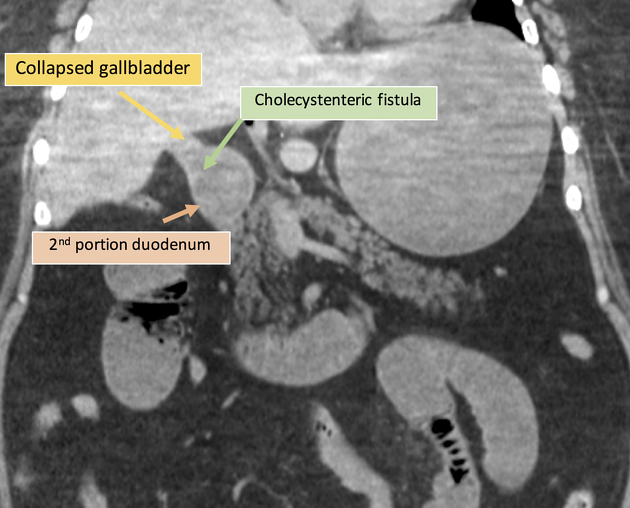

۴. فیستول صفراوی-رودهای

گاهی اوقات اگه دقیق نگاه کنیم، ارتباط غیرطبیعی بین کیسه صفرا و دئودنوم یا روده دیده میشه. شاید subtle باشه، ولی اگه کیسه صفرا تحلیل رفته باشه و یه مقدار هوا هم داخلش باشه، شک ما قویتر میشه.